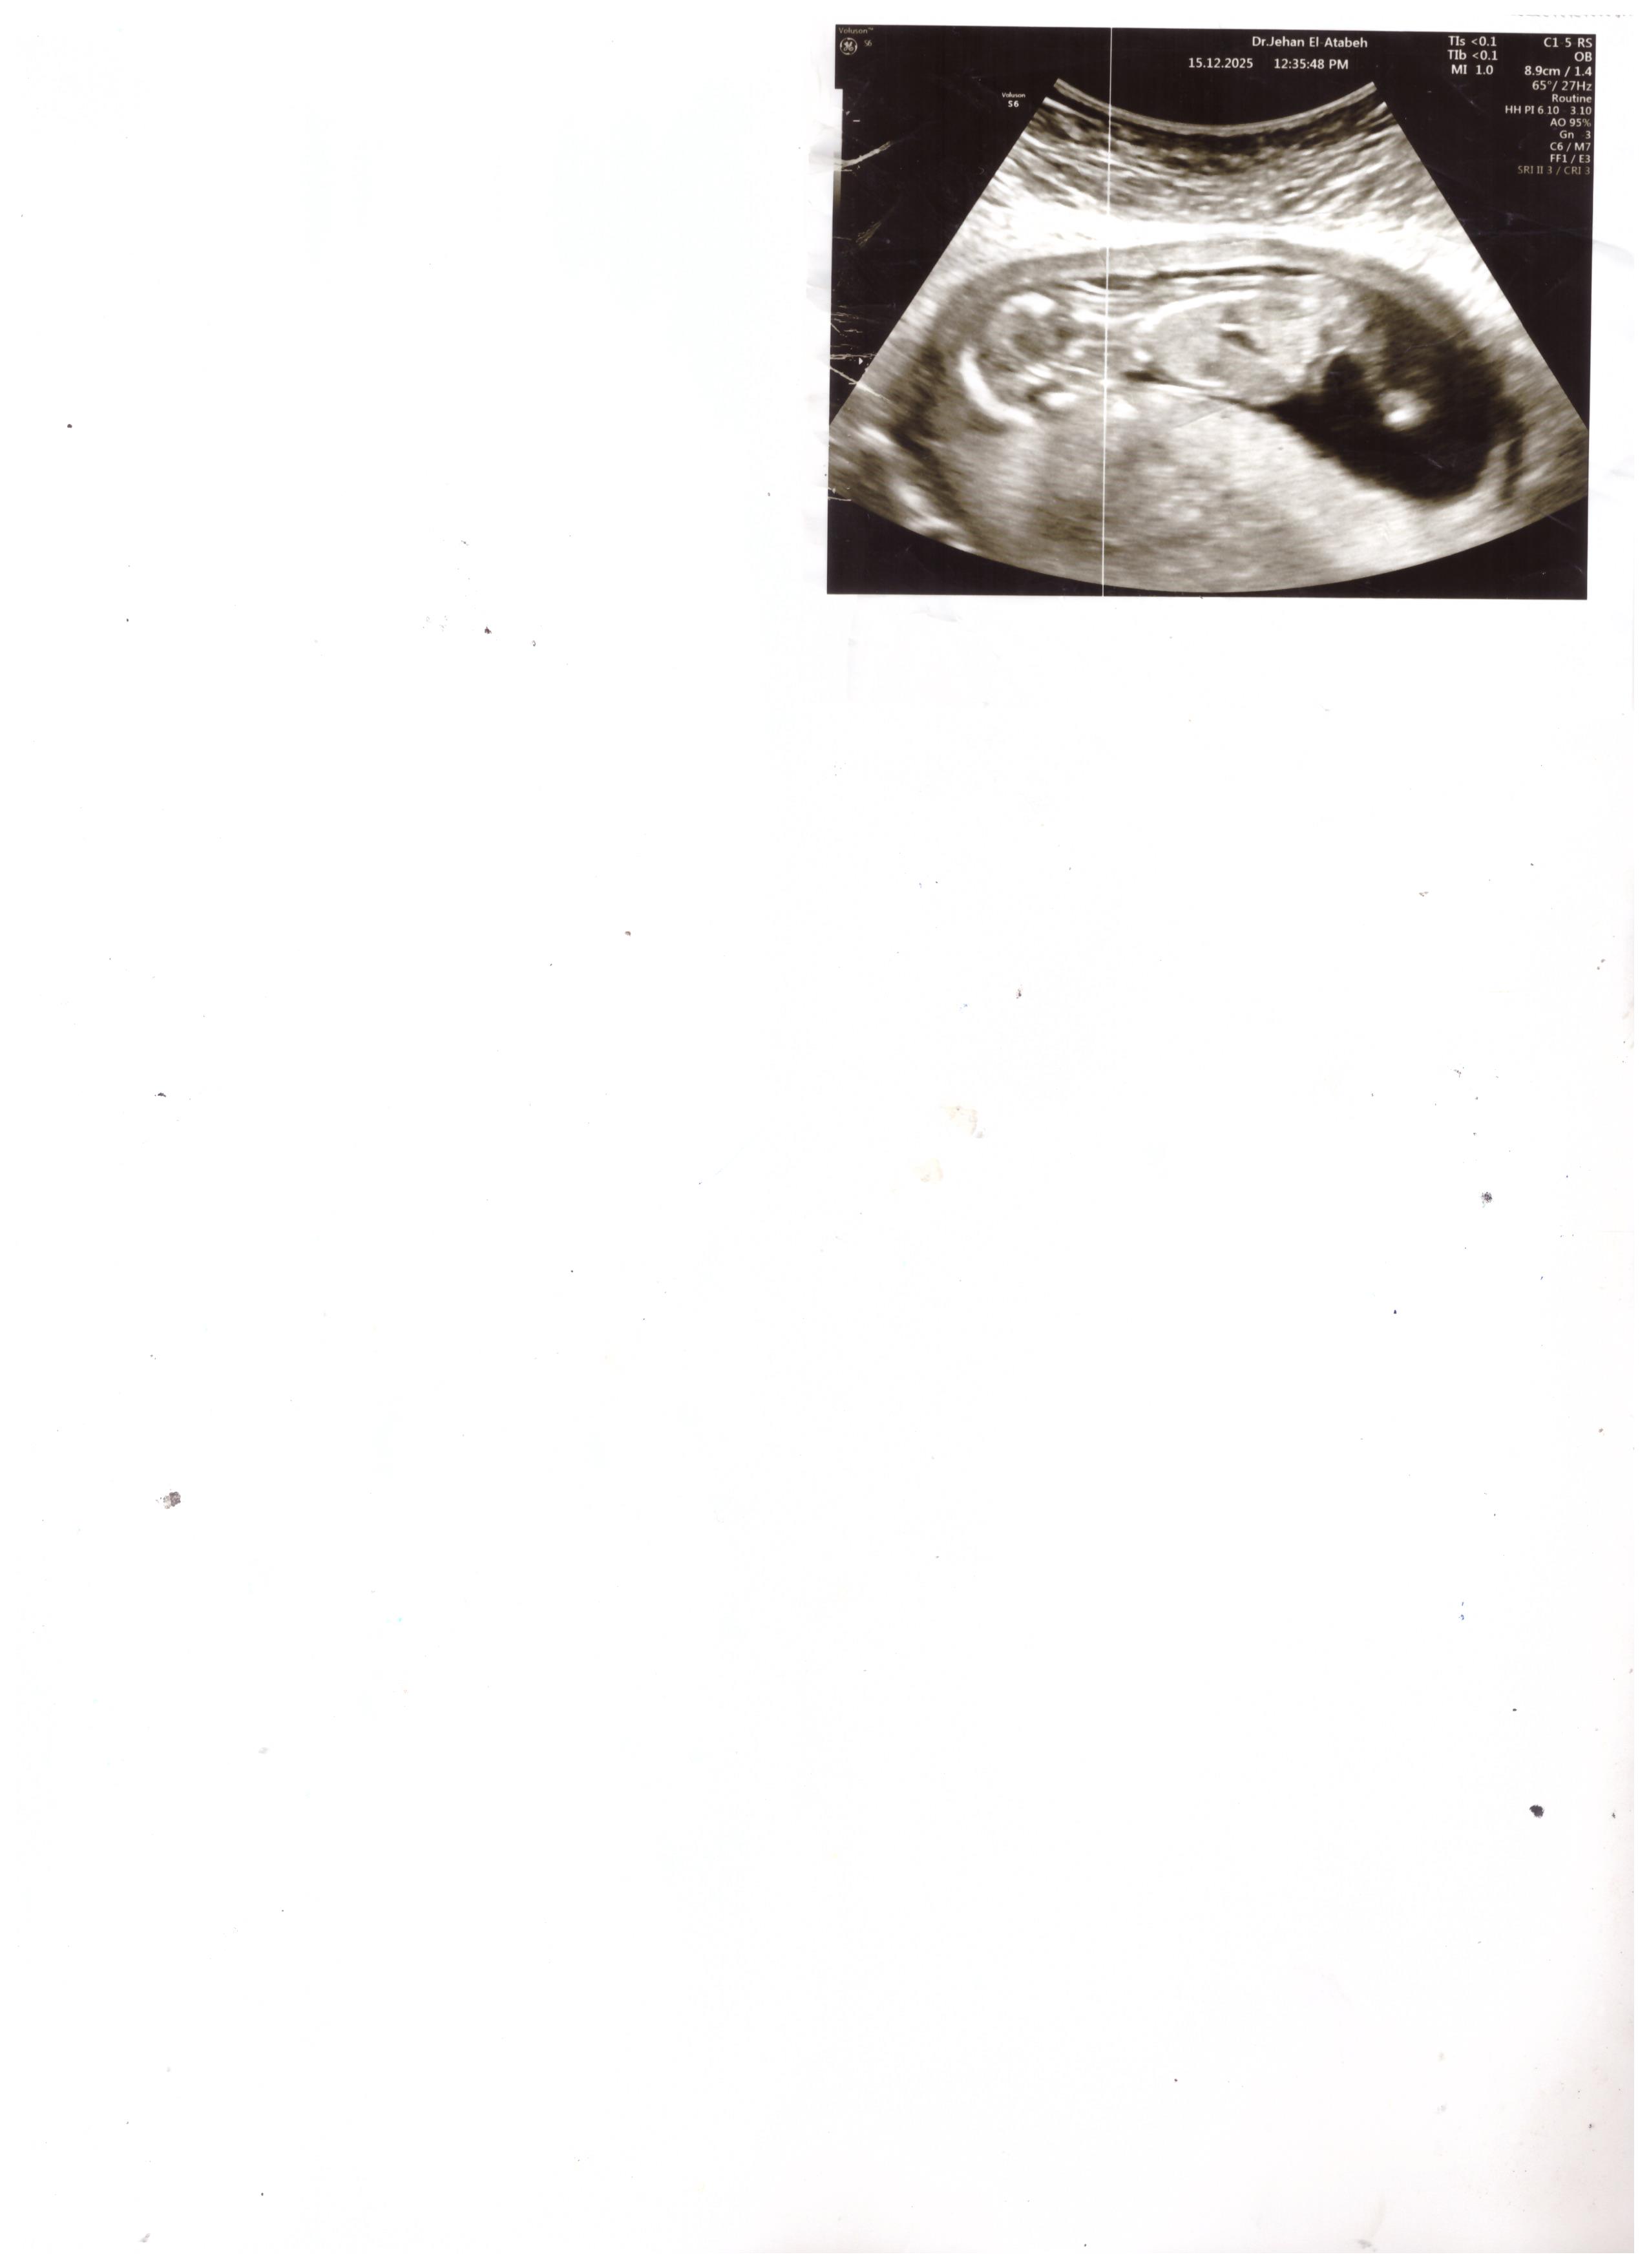

هل يمكنك تحديد جنس المولود من صورة السونار الاسبوع 14؟

صورة جانبية لا تبين نوع الجنين 0 2025-12-16T18:57:19+00:00

صورة جانبية لا تبين نوع الجنين